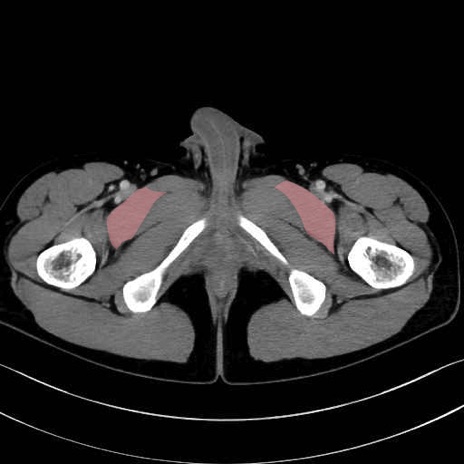

恥骨筋(pubic muscle) のCT画像の解剖

恥骨筋 (Pectineus)